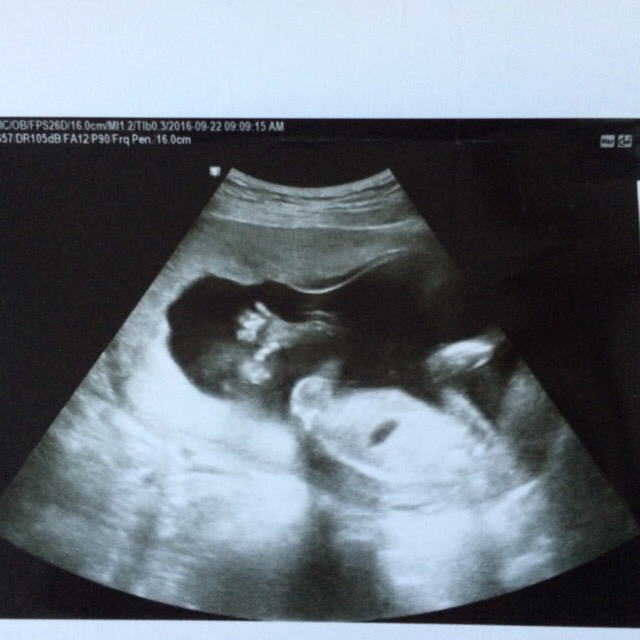

17주 초음파 검사

이어서 초음파 검사! 초음파 검사를 기다리며 엄마 손 꼭 잡고 검사 침대에 누워있으니 의사 선생님이 씩 웃으며 떨리냐고 물어보신다. 딱히 아프거나 이상한 증상은 없더라도 초음파 검사 전에는 항상 떨린다.

어느새 더 쑥- 커버린 우리 행복이.

'엄마 안녕' 하고 손 흔들 듯 다섯손가락을 쫙 펴고 있다니.

콧대가 제대로 잘 생겨야 한다는데, 잘 보이게 옆태를 보여주어 고맙다. 턱선과 콧대에 뿅!

아가의 생식기가 어느 정도 완성되는 16주 즈음부터는 초음파 검사로 태아의 성별을 추측할 수 있다. 우리나라 의료법상 32주 이후에 성별을 알려줄 수 있게 되어있지만, 초음파 사진을 찬찬히 살펴보면 어느 정도 예측이 가능하다. 그래서 더 유심히 지켜본 이번 초음파 검사.

아마도 행복이는 나와 함께 목욕탕을 다닐 것 같다!